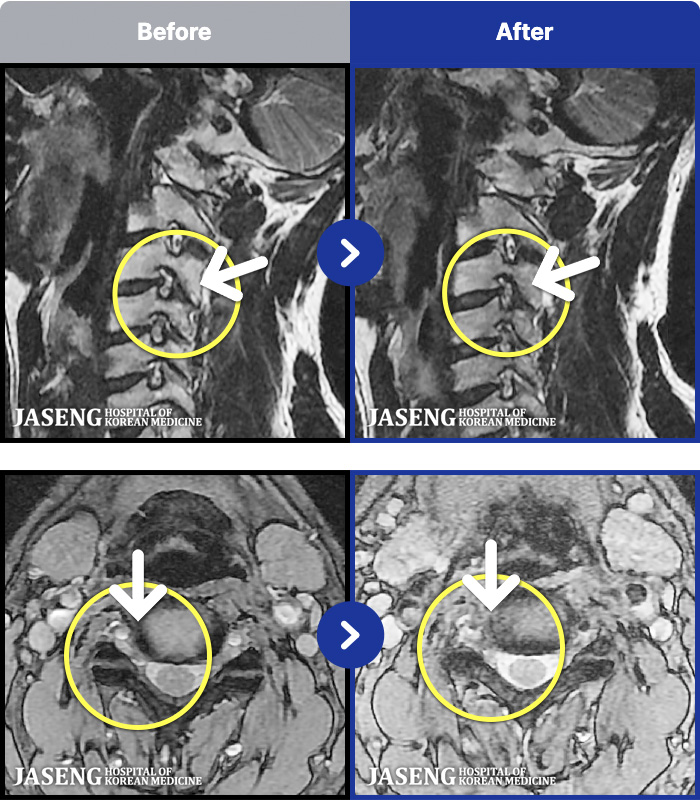

[뱸] 19.11.28~25.05.06